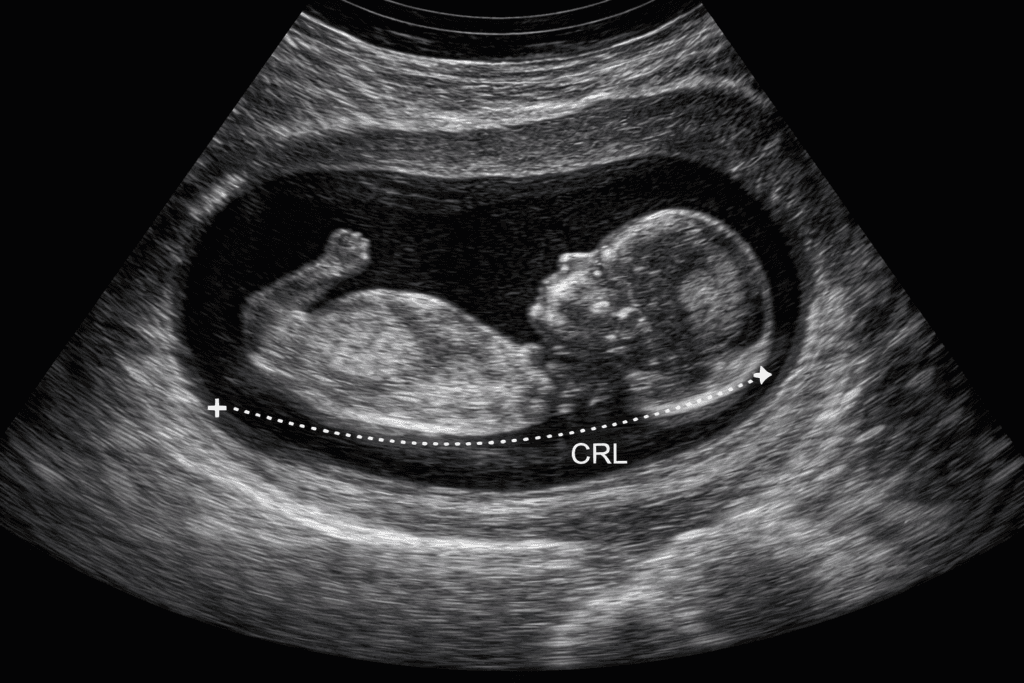

Termijnecho (10–12 weken)

De termijnecho wordt gemaakt wanneer je tussen de 10 en 12 weken zwanger bent. Deze echo is een belangrijk moment in het begin van de zwangerschap: hiermee wordt zo nauwkeurig mogelijk de zwangerschapsduur en de uitgerekende datum vastgesteld. Wat bekijken we tijdens de termijnecho? Tijdens de termijnecho wordt het kindje van bil tot kruin gemeten, […]